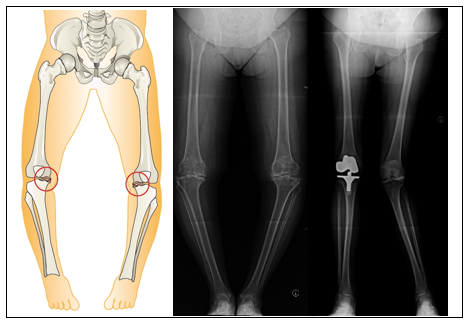

Abbildung 2:

Schematische und radiologische Darstellung der O-Bein- und X-Bein-Arthrose

(Fa. Aesculap und Bildmaterial der Orthopädischen Abteilung, Charité Berlin)